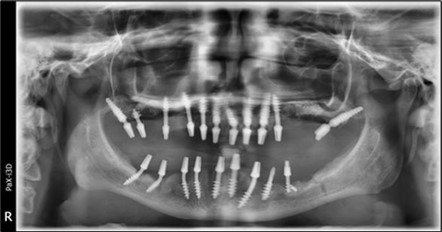

June 2022: Patient presented to our clinic for immediate-loading implant treatment At the time of presentation in 06. 2022, radiologically, advanced peri- implantitis is observed around the implants, with loss of native bone in the affected distal areas (Figure 1)

Figure 1.Panoramic overview picture before rehabilitation 06.2022